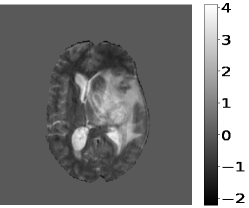

The pre-processing steps on the input MR image and target images are pre-requisites before training the deep learning model. Z-score normalization scales the pixel intensity values of the input MR image to have a mean of zero and a standard deviation of one, and is shown in Figure 2. It is a standard technique in medical imaging to account for variations in image acquisition parameters and to ensure consistent pixel intensity values across different images. The z-score normalization is applied only to brain tissue regions in the MR images, the rest remain unchanged.

The target images have been converted into one-hot vectors. It encodes the segmentation labels as binary vectors, with each dimension corresponding to a distinct label, Edema, NET/NCR, or ET. The normalized input MR images are then stacked. The ground truth and the corresponding one-hot vectors are shown in Figure 3. These pre-processing steps ensure that the input data is in a suitable format for training the deep learning model.